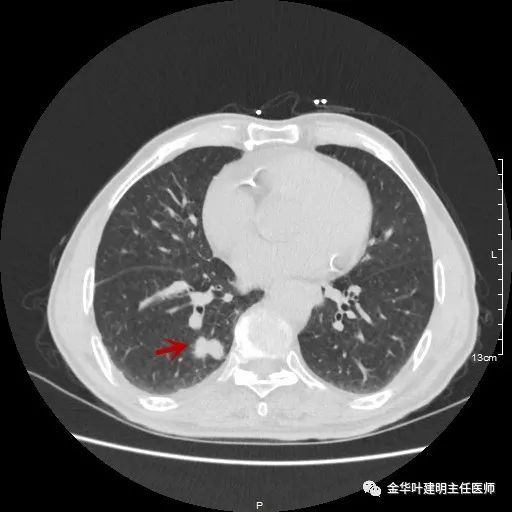

以上示右下叶病灶6。同样是囊腔型病灶,但较前几个范围小,可囊壁同样为磨玻璃影,也是较为典型的囊腔型肺癌表现,单灶来看可下叶背段切除。

如此多的病灶,这样的年纪该如何考虑?我们先来分一下:病灶3与病灶5是混合磨玻璃及实性病灶,不能继续观察等待,得干预;病灶1、病灶4与病灶6是囊腔型肺癌考虑,恶性程度低,可观察随访,若处理病灶3与5的话,能附带则要附带处理;病灶2在左侧,目前较小,而且在肺外周部位,若对右侧进行干预,则左侧先观察随访,下次可考虑局部楔形切除。